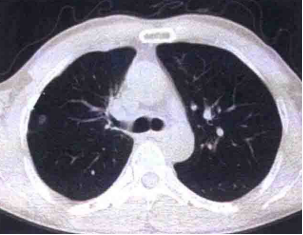

图1 胸部CT

本病例以单纯发热为唯一首发症状,咳嗽、咳痰等呼吸道表现并不典型,早期胸部CT仅提示右肺上叶前段结节性病灶,易被误诊为普通上呼吸道感染或

从肺部影像学来看,本例最初仅表现为局限于右肺上叶前段的结节影,但短时间内即演变为双肺弥漫性渗出、实变,还合并胸腔积液,这类表现虽提示肺部感染,却与继发性肺结核等疾病存在较多重叠,单纯依靠胸部影像难以实现精准鉴别,直接确诊难度极大,因此病原学检查成为明确诊断的关键——临床在应用抗生素前留取多部位标本进行培养,最终从血培养和痰培养中均检出类鼻疽伯克霍尔德氏菌,这也是类鼻疽感染确诊的金标准,后续结合药敏试验调整为亚胺培南西司他丁钠联合卡泊芬净等方案后,患者感染逐步得到控制,也进一步验证了病原学指导下精准治疗的有效性。

在影像学上,类鼻疽肺炎同样表现多样,早期以上叶受累多见,随病情进展会逐渐累及多肺叶,极易与继发性肺结核混淆,进一步凸显了病原学检查的核心价值——尽管多数病例在病原学结果回报前难以直接确诊,且病情进展快、早期经验性治疗效果不佳,是患者转入重症监护室的重要原因,但临床若能结合患者的地域暴露史、高危因素、症状体征及影像学特点,早期考虑到类鼻疽感染可能并启动经验性治疗(目前首选亚胺培南、